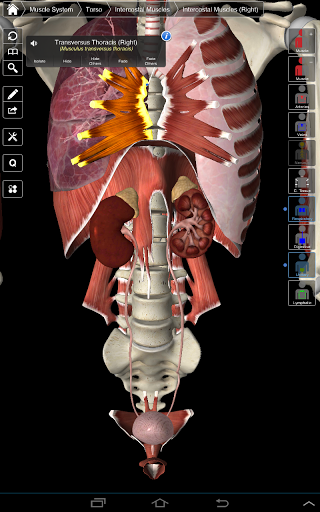

Essential Anatomy 3 representa lo último en tecnología 3D innovadora y diseño innovador. Un motor de gráficos 3D de vanguardia, creado a medida por 3D4Medical desde cero, alimenta un modelo anatómico altamente detallado y ofrece gráficos de calidad excepcional que ningún otro competidor puede lograr.

La aplicación representa un enfoque único para el aprendizaje de la anatomía general. Los gráficos no tienen paralelo y hacen que el aprendizaje, a través del uso de contenido informativo y características innovadoras, sea una experiencia rica e interesante.

⁃Músculos

NUEVA TECNOLOGÍA 3D

Essential Anatomy 3 es receptivo, visualmente impactante y sin esfuerzo. La aplicación es totalmente en 3D, lo que significa que puedes ver cualquier estructura anatómica de forma aislada y desde cualquier ángulo.

La funcionalidad inteligente que se encuentra dentro de la aplicación permite al usuario eliminar capas de músculo a través de la herramienta 'bisturí'. Esta aplicación ofrece a los usuarios la posibilidad de activar / desactivar sistemas sin la necesidad de anular la selección de estructuras individuales o mezclarse en una multitud de pestañas regionales predefinidas, como otras aplicaciones.

---- Más de 4,000 estructuras anatómicas altamente detalladas